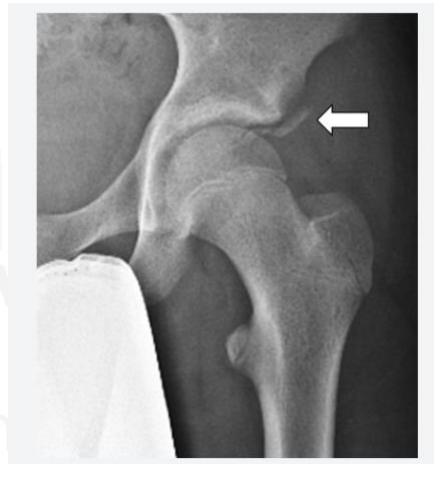

A teenager with acute onset of pain in the right hip during a run. He sustained the injury seen in the x-rays with a white arrow. This injury usually occurs due to a forceful eccentric contraction of which of the following muscles?

- C. Rectus femoris

- Sartorius

Pelvic Anatomy

Which of the following muscles is attached to the structure pointed by the arrow?

- C. Sartorius

Note: Arrow was pointing at ASIS (Anterior Superior Iliac Spine)